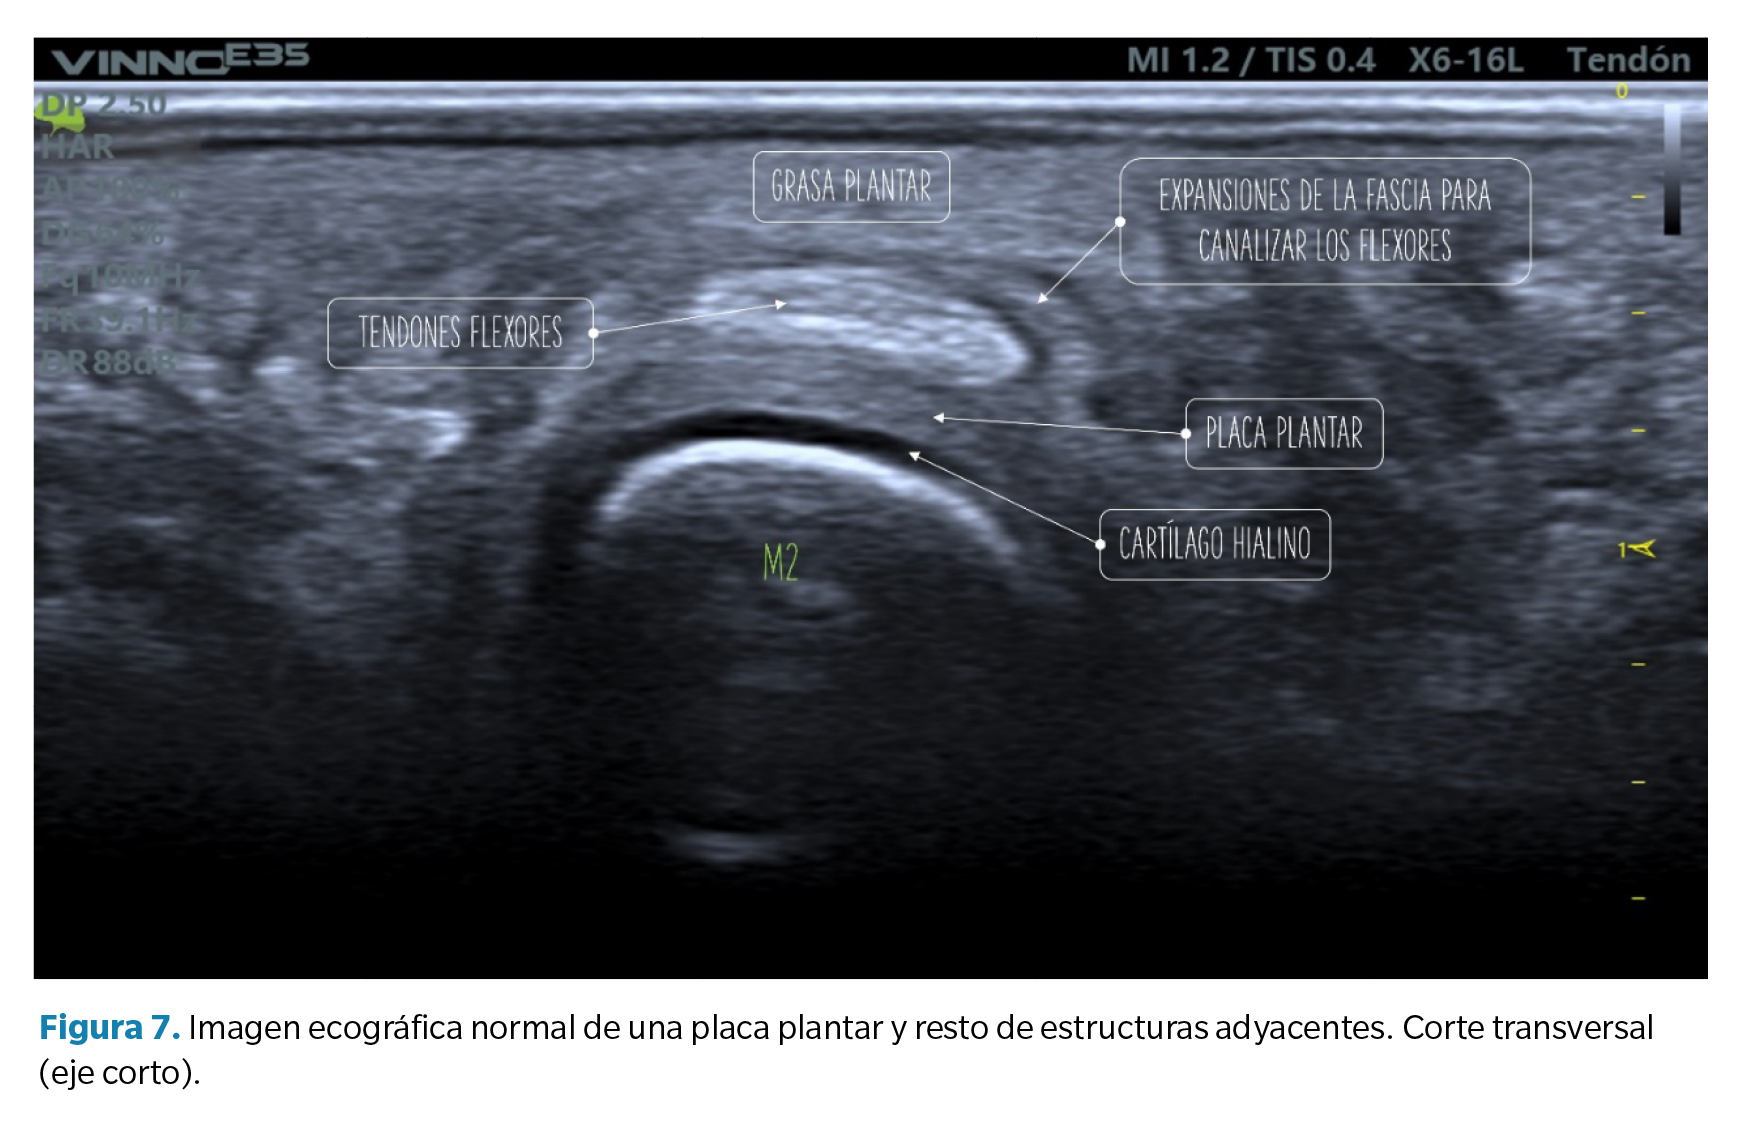

- Corte transverso (eje corto): la placa plantar tendrá una forma curvada que acuna a la cabeza metatarsal. La ecotrama es igualmente granulada, si bien en este corte el aspecto del moteado puede ser más heterogéneo al reflejar la disposición longitudinal de los haces de colágeno. Sobre la placa se revelan los tendones flexores que pueden identificarse fácilmente mediante maniobras de anisotropía (Figura 7).